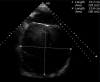

Figure 2

Echocardiogram in apical four-chamber view showing an enlarged left atrium measuring 140×143 mm.